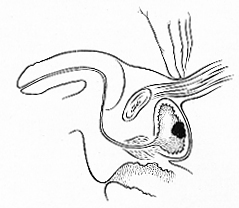

Pulpitele cronice

Pulpitele cronice Obs. Refacerea lucrarii de control pe 27.Ian.2001 (Sambata) ora 10:00 q Pulpitele cronice sunt de doua tipuri: · inchise ·&nbsCiteste tot ... 1211 cuvinte

Dimensiune mica

+ cu imagini |